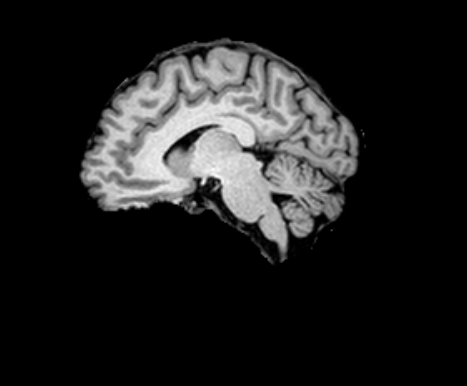

3.1.2 Segmentation

We used SynthSeg [6] (with the --parc option) to quickly (in less than a minute) produce FreeSurfer-like segmentations of the moving and reference images into 98 anatomical regions following the Desikan–Killiany–Tourville (DKT) protocol depicted in [39, 17]. For evaluation purposes, we grouped the labels into three anatomical groups: sub-cortical (labels: 10, 11, 12, 13, 17, 18, 26, 28, 49, 50, 51, 52, 53, 54, 58 and 60), cortical (labels greater than 1000) and white matter (super labels 2 and 41). When computing metrics for these groups, we report the average over the individual labels within each group, without merging the regions into a single aggregated label.